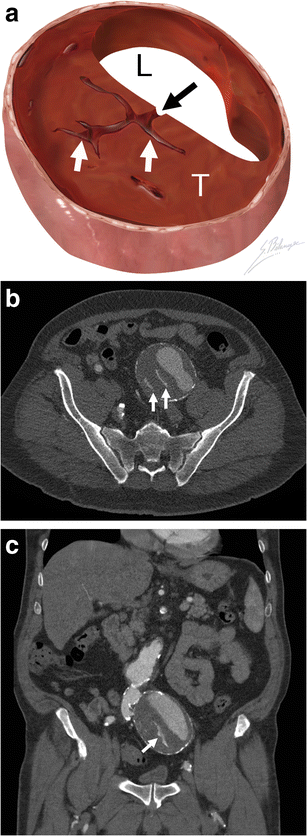

Hyperattenuating crescent sign. a Illustration demonstrates blood (black arrow) dissecting into a mural thrombus (T) from the aortic lumen (L). The resulting intramural haematoma (H) is crescent shaped. b Axial unenhanced CT of a 63-year-old man presenting with abdominal pain and a pulsating mass. A crescent (H) of higher attenuation than the aortic lumen (L) can be seen

Thrombus fissuration

Thrombus fissuration. a Illustration demonstrates blood (black arrow) dissecting from the aortic lumen (L) into a mural thrombus (T). The infiltrating blood is seen as linear fissurations (white arrows). b Axial and c coronal enhanced CT of a 64-year-old man shows linear infiltrations of contrast material (white arrows) within the hypodense mural thrombus. The patient underwent successful emergent AAA repair before complete rupture occurred